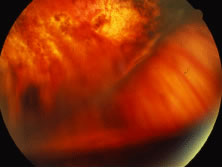

Others and we have reported a high incidence (up to 22%) of rhegmatogenous retinal detachment in association with ganciclovir treatment for CMV retinitis.115 The presence of chronic inflammation in these eyes may be important in the pathogenesis of proliferative vitreoretinopathy and retinal detachment (Figs. 24, 25, and 26). Inflammatory products and cells may contribute to contraction of the vitreous gel by stimulating migration of contractile cells or by metaplasia of macrophages into contractile elements that contribute to posterior vitreous detachment.105

Fig. 24. Rhegmatogenous retinal detachment associated with cytomegalovirus (CMV) retinitis. The retina is extremely thin and filled with atrophic breaks; these are best seen in the superior aspect of the illustration.

Fig. 25. Proliferative vitreoretinopathy (PVR) manifest by star fold is seen in a patient with rhegmatogenous retinal detachment associated with healed cytomegalovirus retinitis. PVR is very unusual in cytomegalovirus (CMV) retinitis, however, it may occur in associated with immune recovery uveitis.

Fig. 26. A case of rhegmatogenous retinal detachment associated with cytomegalovirus (CMV) treated successfully with peripheral retinal laser, vitrectomy, and buckling. Note that the silicone oil does not provide inferior tamponade. There is a shallow detachment between the posterior edge of the scleral buckle and the area of peripheral scatter laser that has prevented progressive retinal detachment.

Treatment of retinal detachment in these eyes must address the multiple retinal breaks, many of which may be difficult to visualize, as well as the propensity of these eyes to develop proliferative vitreoretinopathy. In addition, these patients suffer from serious concurrent systemic diseases. For these reasons, primary pars plana vitrectomy with internal retinal tamponade is appropriate. Silicone oil offers long-acting tamponade to the extensive areas containing retinal breaks, as well as to areas of potential future retinal breaks in zones of retinitis. This tamponade makes destructive and inflammatory use of widespread retinopexy unnecessary. Extensive scleral buckling may be avoided. In our experience with this technique, eyes with silicone oil completely filling the vitreous cavity have retained clear lenses from 1 to 7 months after surgery. These lenses may remain clear for a longer time than do other phakic eyes containing silicone oil because they have not suffered the trauma of multiple prior surgical procedures. In all cases in our series, retinas have remained attached after vitrectomy and repair with silicone oil. Treatment of the retinitis with foscarnet or ganciclovir appears not to be affected by the use of intravitreal silicone oil.